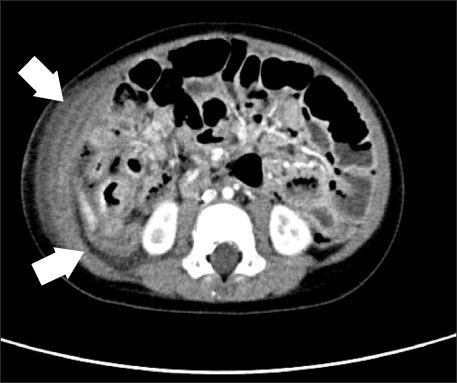

Fig. 2

Abdominal CT shows suspicious intraperitoneal and retroperitoneal abscess with air collection due to suspicious bowel perforation (white arrows).

We considered this patient as bacterial enteritis and started symptomatic treatment. On the 3rd hospital day, the patient suddenly showed massive bloody stool. His vital signs were as follows: blood pressure, 95/70 mmHg; heart rate, 93 beats/min; respiratory rate, 21 breaths/min; and temperature, 39.5℃. Physical examination on abdomen showed rigidity, voluntary guarding and tenderness on palpation in the entire abdominal area. Bowel sounds were decreased. Laboratory data were as follows: sodium, 140 mEq/L; potassium, 3.3 mEq/L; chloride, 102 mEq/L; BUN/creatinine, 2.7/0.32 mg/dL; CRP, 118 mg/dL; and glucose, 93 mg/dL. The CBC was as follows: WBC, 15,420/µL; neutrophils, 69.4%; Hb/Hct, 8.9/26.6%; and platelets, 346,000/µL. Abdominal CT showed suspicious intraperitoneal and retroperitoneal abscess with air collection due to possible bowel perforation (Fig. 2).

Fig. 2 Abdominal CT shows suspicious intraperitoneal and retroperitoneal abscess with air collection due to suspicious bowel perforation (white arrows).